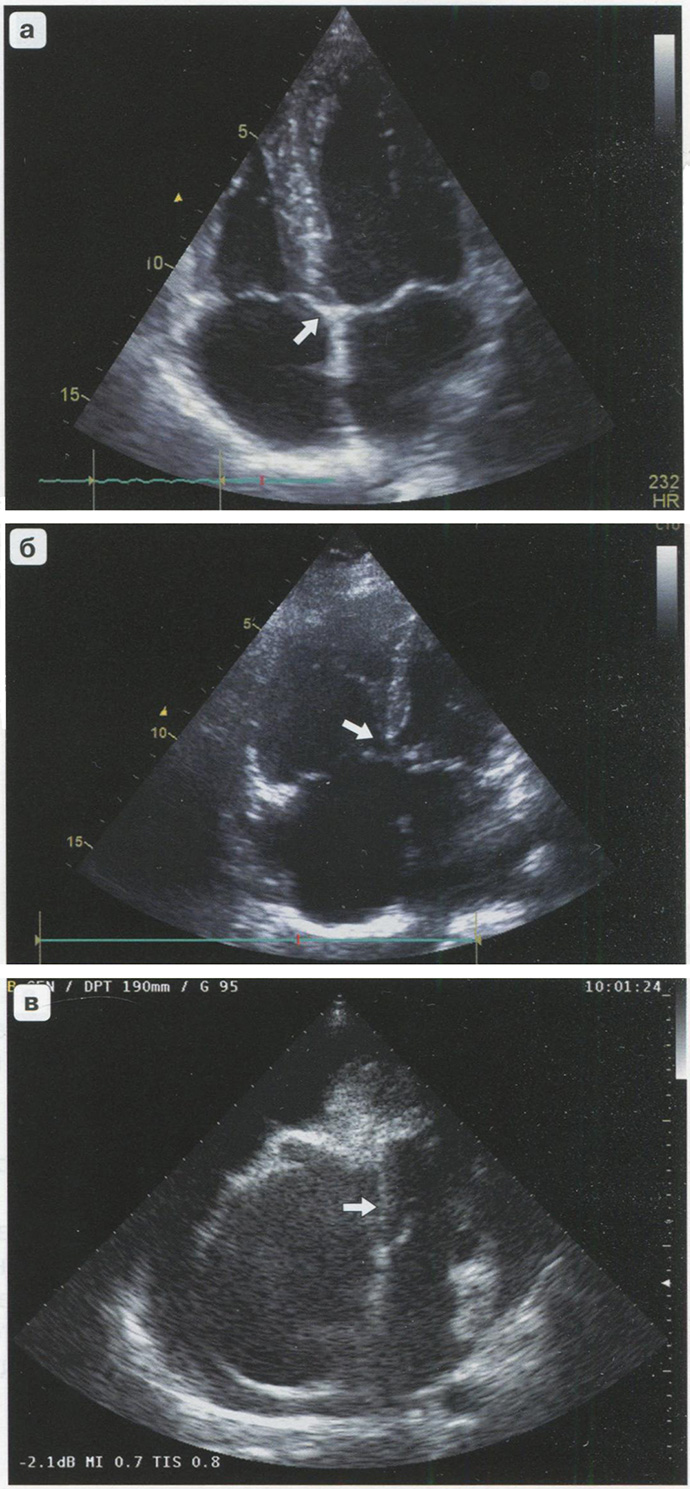

Оценка крепления фиброзных колец

В норме правое и левое фиброзные кольца крепятся на различном уровне: правое фиброзное кольцо смещено по отношению к левому в полость правого желудочка. Правое фиброзное кольцо в норме смещено в полость правого желудочка до 7 мм. Если фиброзные кольца расположены на одном уровне, то имеет место один из врожденных пороков сердца (низкий дефект межпредсердной перегородки, полный атриовентрикулярный канал и т.д.) (рис. 2.2).

Рис. 2.2. Варианты крепления левого и правого фиброзных колец. В-режим. Апикальная четырехкамерная позиция, а - нормальное крепление фиброзных колец (стрелка); б - крепление фиброзных колец на одном уровне (стрелка); в - разница в креплении фиброзных колец > 7 мм - аномалия Эбштейна (стрелка).